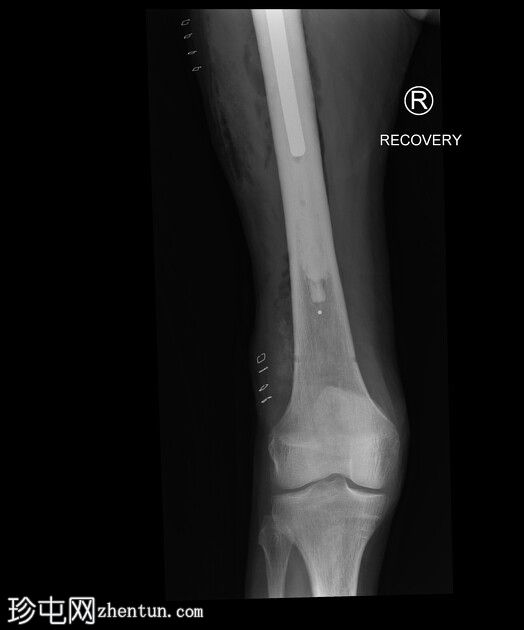

X光片

3.jpeg

侧面

右侧髓内钉近端骨折(位于拉力螺钉孔位)。

空心髋螺钉组件完好。

股骨转子间骨折延伸至股骨近端转移灶,小转子粉碎。

以下为既往(及随访)影像学检查结果,供参考,展示术前股骨近端溶骨性病变、髓内钉骨折前的表现以及髓内钉骨折后的治疗情况。